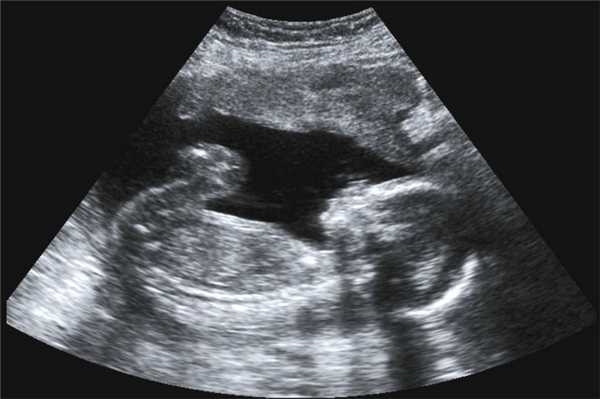

Фото УЗИ ребенка на разных сроках беременности

Если беременность желанная, будущие родители внимательно относятся к пренатальной диагностике плода. Чтобы убедится, что ребенок развивается нормально, в течение 9 месяцев гинеколог несколько раз направляет женщину на ультразвуковое исследование. Фото УЗИ может многое рассказать врачу и будущим родителям о малыше. Кроме того, снимок станет трогательным напоминанием для семейного архива.

Чтобы сделать фото УЗИ малыша на разных сроках, беременной женщине необходимо записаться на ультразвуковой скрининг в медицинском центре «Диана».

Информативность ультразвука зависит от вида исследования. Сегодня для диагностики плода используют такие виды УЗИ:

- 2D УЗИ . Это самый распространенный метод УЗИ, который применяется на всех сроках беременности. Исследование проходит по двум параметрам - по ширине и высоте. В результате процедуры получают плоское черно-белое фото. Время проведения исследования обычно составляет от 15 до 20 минут.